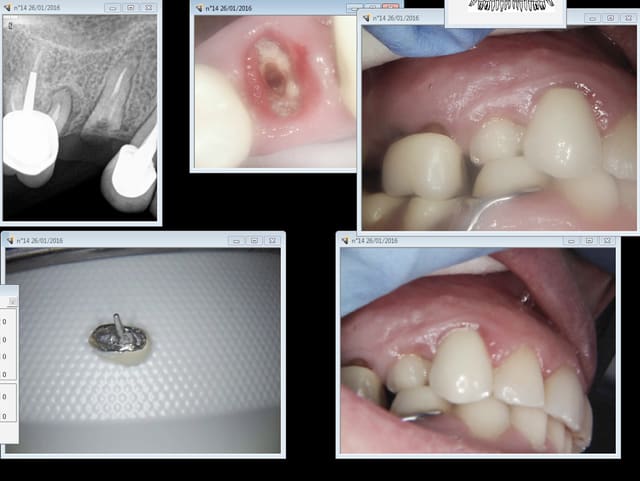

Autre cas : bouche motocross, 14 en vrac ca va se "voir". ptt svp et avec un minimum de reste à charge sinon c'est pas marrant. -)

Capture d e cran 2016 01 26 14.04 - Eugenol